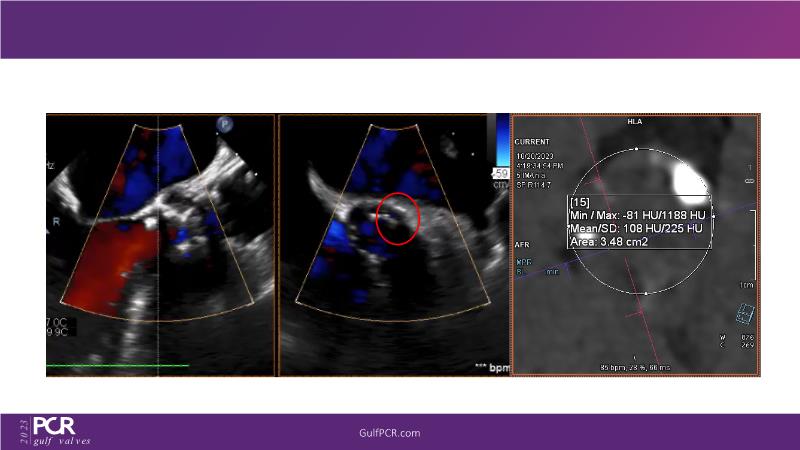

The primary focus of this GulfPCR-GIM 2023 session revolves around pre-procedural planning considerations, valve selection, and managing complex anatomies using both traditional self-expanding valves and the Evolut FX system. Additionally, the session aims to explore the work-up protocol for patients grappling with severe AS and advanced CKD, elucidate the algorithm for selecting the appropriate TAVR platform, discuss strategies to reduce contrast utilization, and highlight the distinctive advantages offered by the Evolut FX system.

• To discuss challenges in TAVI procedural planning

• To discuss valve choice in challenging anatomies